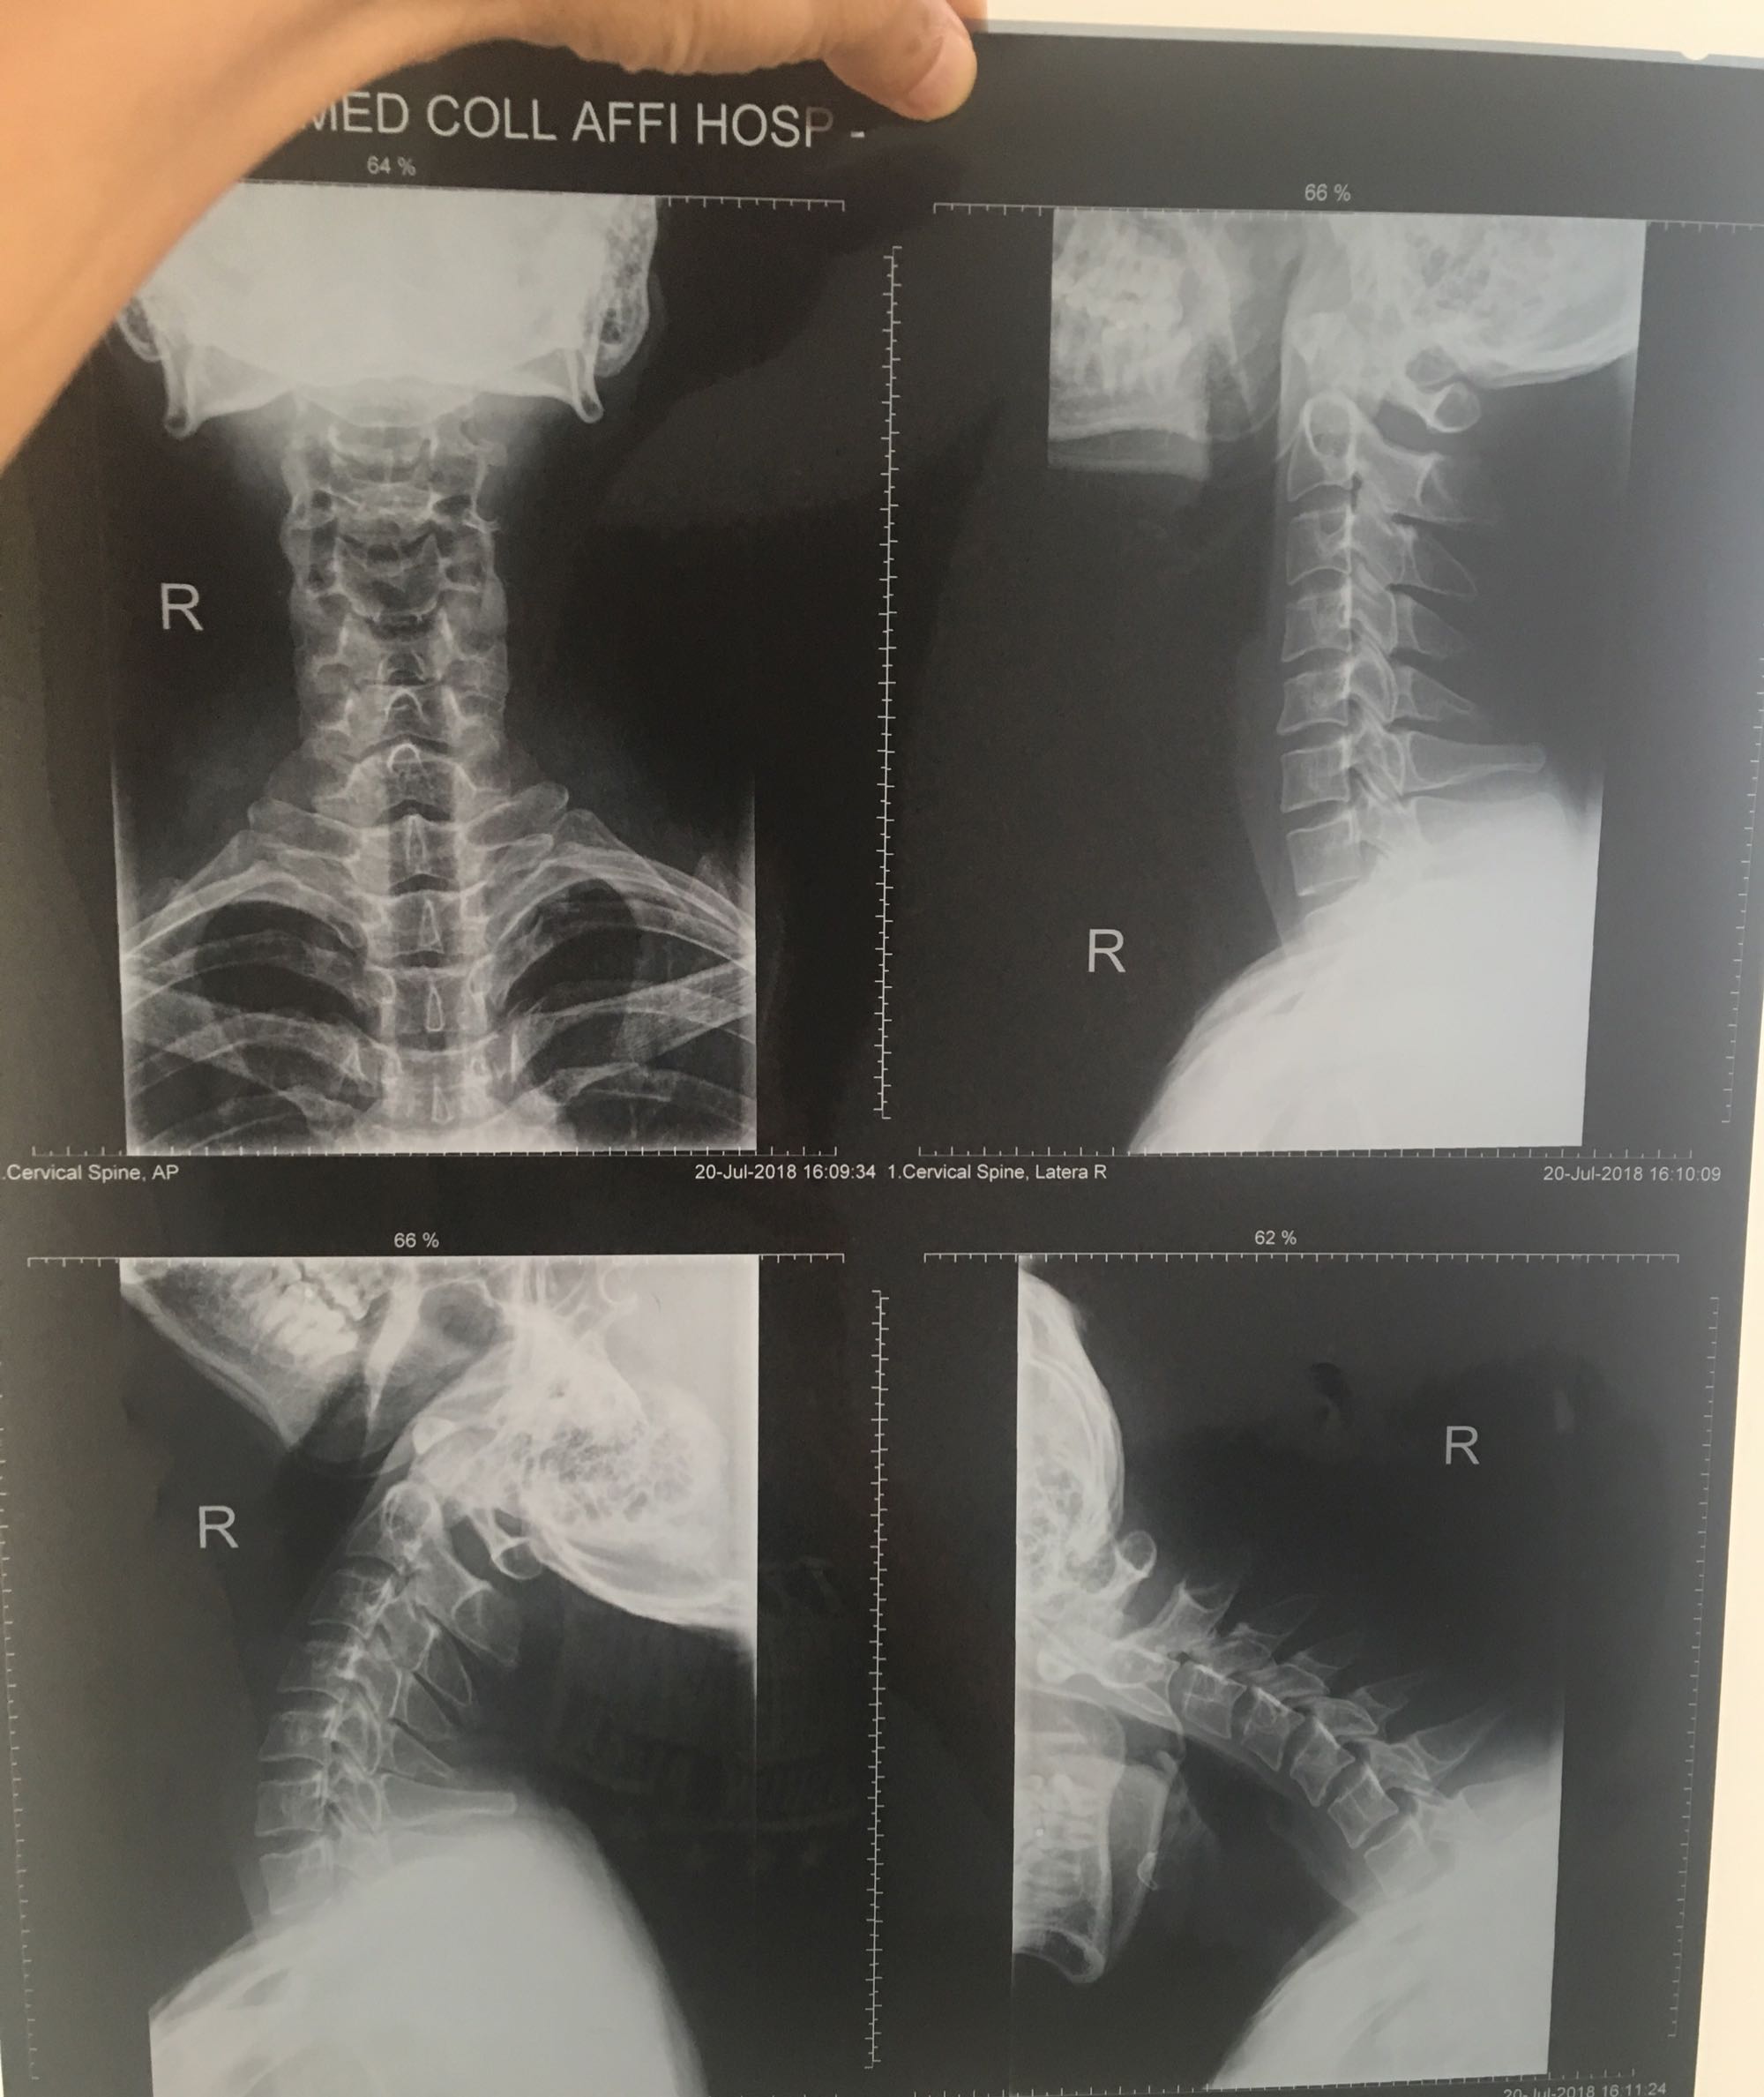

颈椎曲度变直是不是没办法再回到正常的曲度了?

我经常头晕,去医院照片说颈椎曲度变直了。

我这个算严重吗?

345.67胸1.有错位

突出了